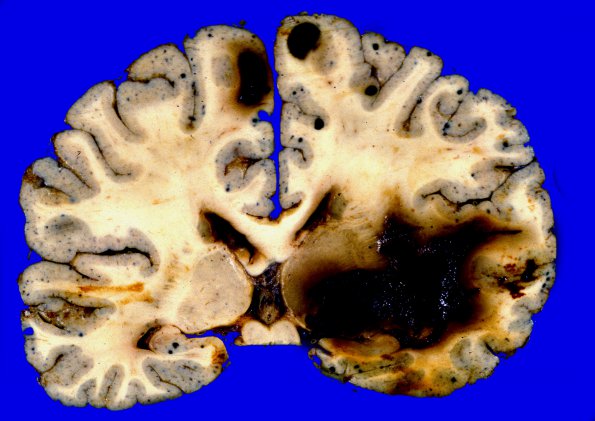

Washington University Experience | NEOPLASMS (METASTASES) | Melanoma | 1A2 Metastases Melanoma (Case 1) 2

1A2 Metastases Melanoma (Case 1) 2

he extent of cortical involvement is amazing with metastases ranging from several centimeters to pinpoint.